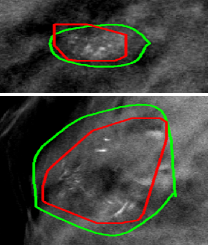

4.2 Performance on DBT Volume Image

The proposed system was tested on an independent GE SenoClaire DBT volume set with 23 labeled malignant MC groups and 42 normal cases, no individual MC labeled and no other abnormalities visible. Figure 4(a) shows the MC group detection FROC and the comparison with other previously published MC group detection performances on DBT [1, 2, 3, 4, 5, 10]. Figure 4(b) shows two successful detections. The proposed system shows state-of-the-art performance compared with these published works, although all these works including ours were tested on different and relatively small datasets ( cancerous lesions). We need to emphasize that there was absolutely no training or fine-tuning on the DBT data for our system, while other works were not restricted to develop on small numbers of DBTs that could cause overfitting. The study from Morra et al. [10] reported better performance, but the authors used Hologic cases with two-view DBT volumes per breast, which may double the chance to find MC groups, while the GE set we were using had only one DBT view available. Furthermore, there is no method details disclosed in [10].